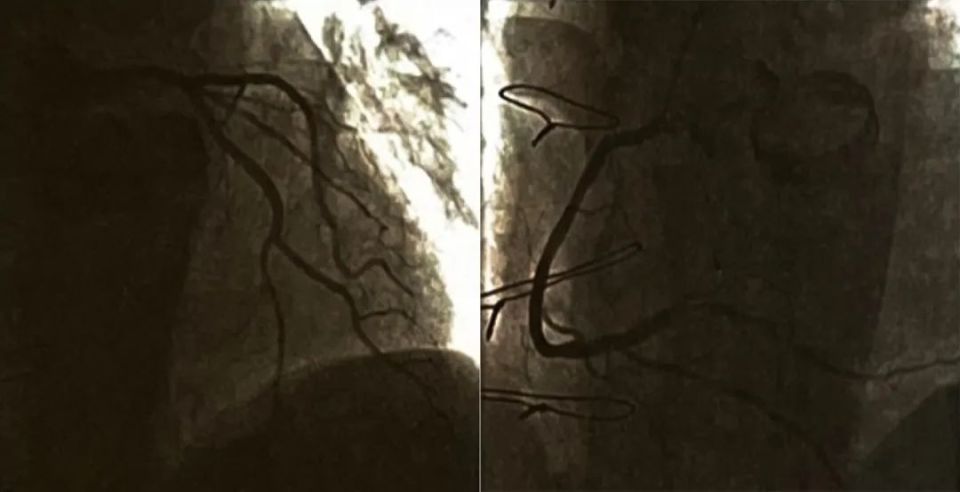

随访:患者术后多次门诊复查,活动耐量可,偶有轻度胸痛发作,与活动无关,程度不重。定期监测INR,术后40余天复查门诊心电图示(图3):窦性心律,下壁异常Q波,T波改变。超声心动图示:左心室大小正常,左心室下壁运动稍减低,EF 52%。行冠状动脉造影复查(图4),见LAD、LCX正常,RCA支架通畅,血流正常。

图4. 第三次复查冠状动脉造影:LCA正常,RCA支架通畅,血流正常